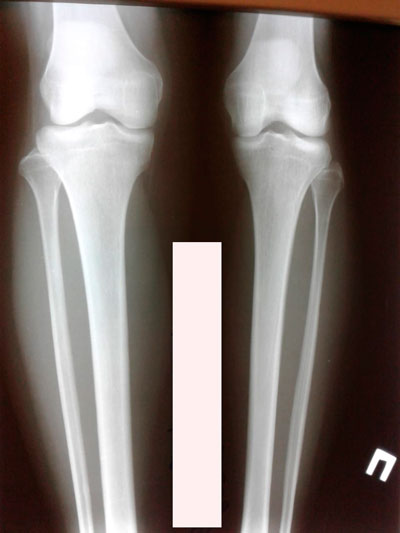

Исходник - 24 года.

Диагноз: врождённое укорочение правой голени на 4 см.

Дата операции - 10.07.2019г.

рентген в процессе удлинения